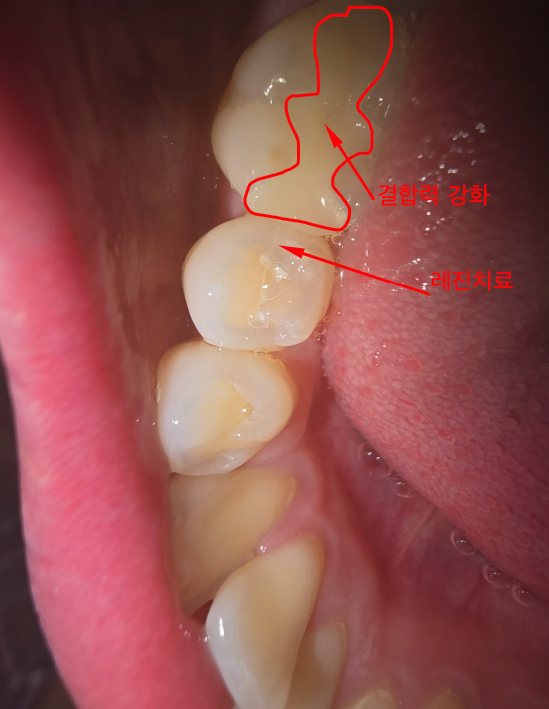

충치만 따지고 봤을때 본체 인레이 1개 30만원, 양옆 어금니 레진치료 각각 10만원해서 50만원이다.

보다시피 오른쪽 아래 어금니 1, (2, 3), 4 구역 모두 썪은 상황이다.

1은 가장 뒤 어금니, (2, 3)은 뒤에서 두번째 어금니, 4는 뒤에서 세번째 어금니였다.

자책과 별개로 치료는 시작되었고 오른쪽 사진처럼 깔끔하게 제거된 것을 확인할 수 있다.

나는 내 치아를 최대한 지키고자 2번과 3번구역 각각 치료가 가능한지 여쭤보았다.

2구역과 3구역만 파내서 따로따로 보철물을 접착하기엔 결합력이 약하다고 한다.

그래서 보통 2구역과 3구역을 모두 제거하여 이어지는 보철물을 끼운다고 한다.

그래야 결합력이 강해지는 구조를 만들 수 있다.

벼랑끝에 매달려 있는것보다는 가로질러 박혀있는게 당현히 결합력이 좋을 수 밖에 없지.

2월 4일 본뜬 보철물로 빈공간을 채웠다.

지금은 완전히 잘 치료된 모습을 볼 수 있다.